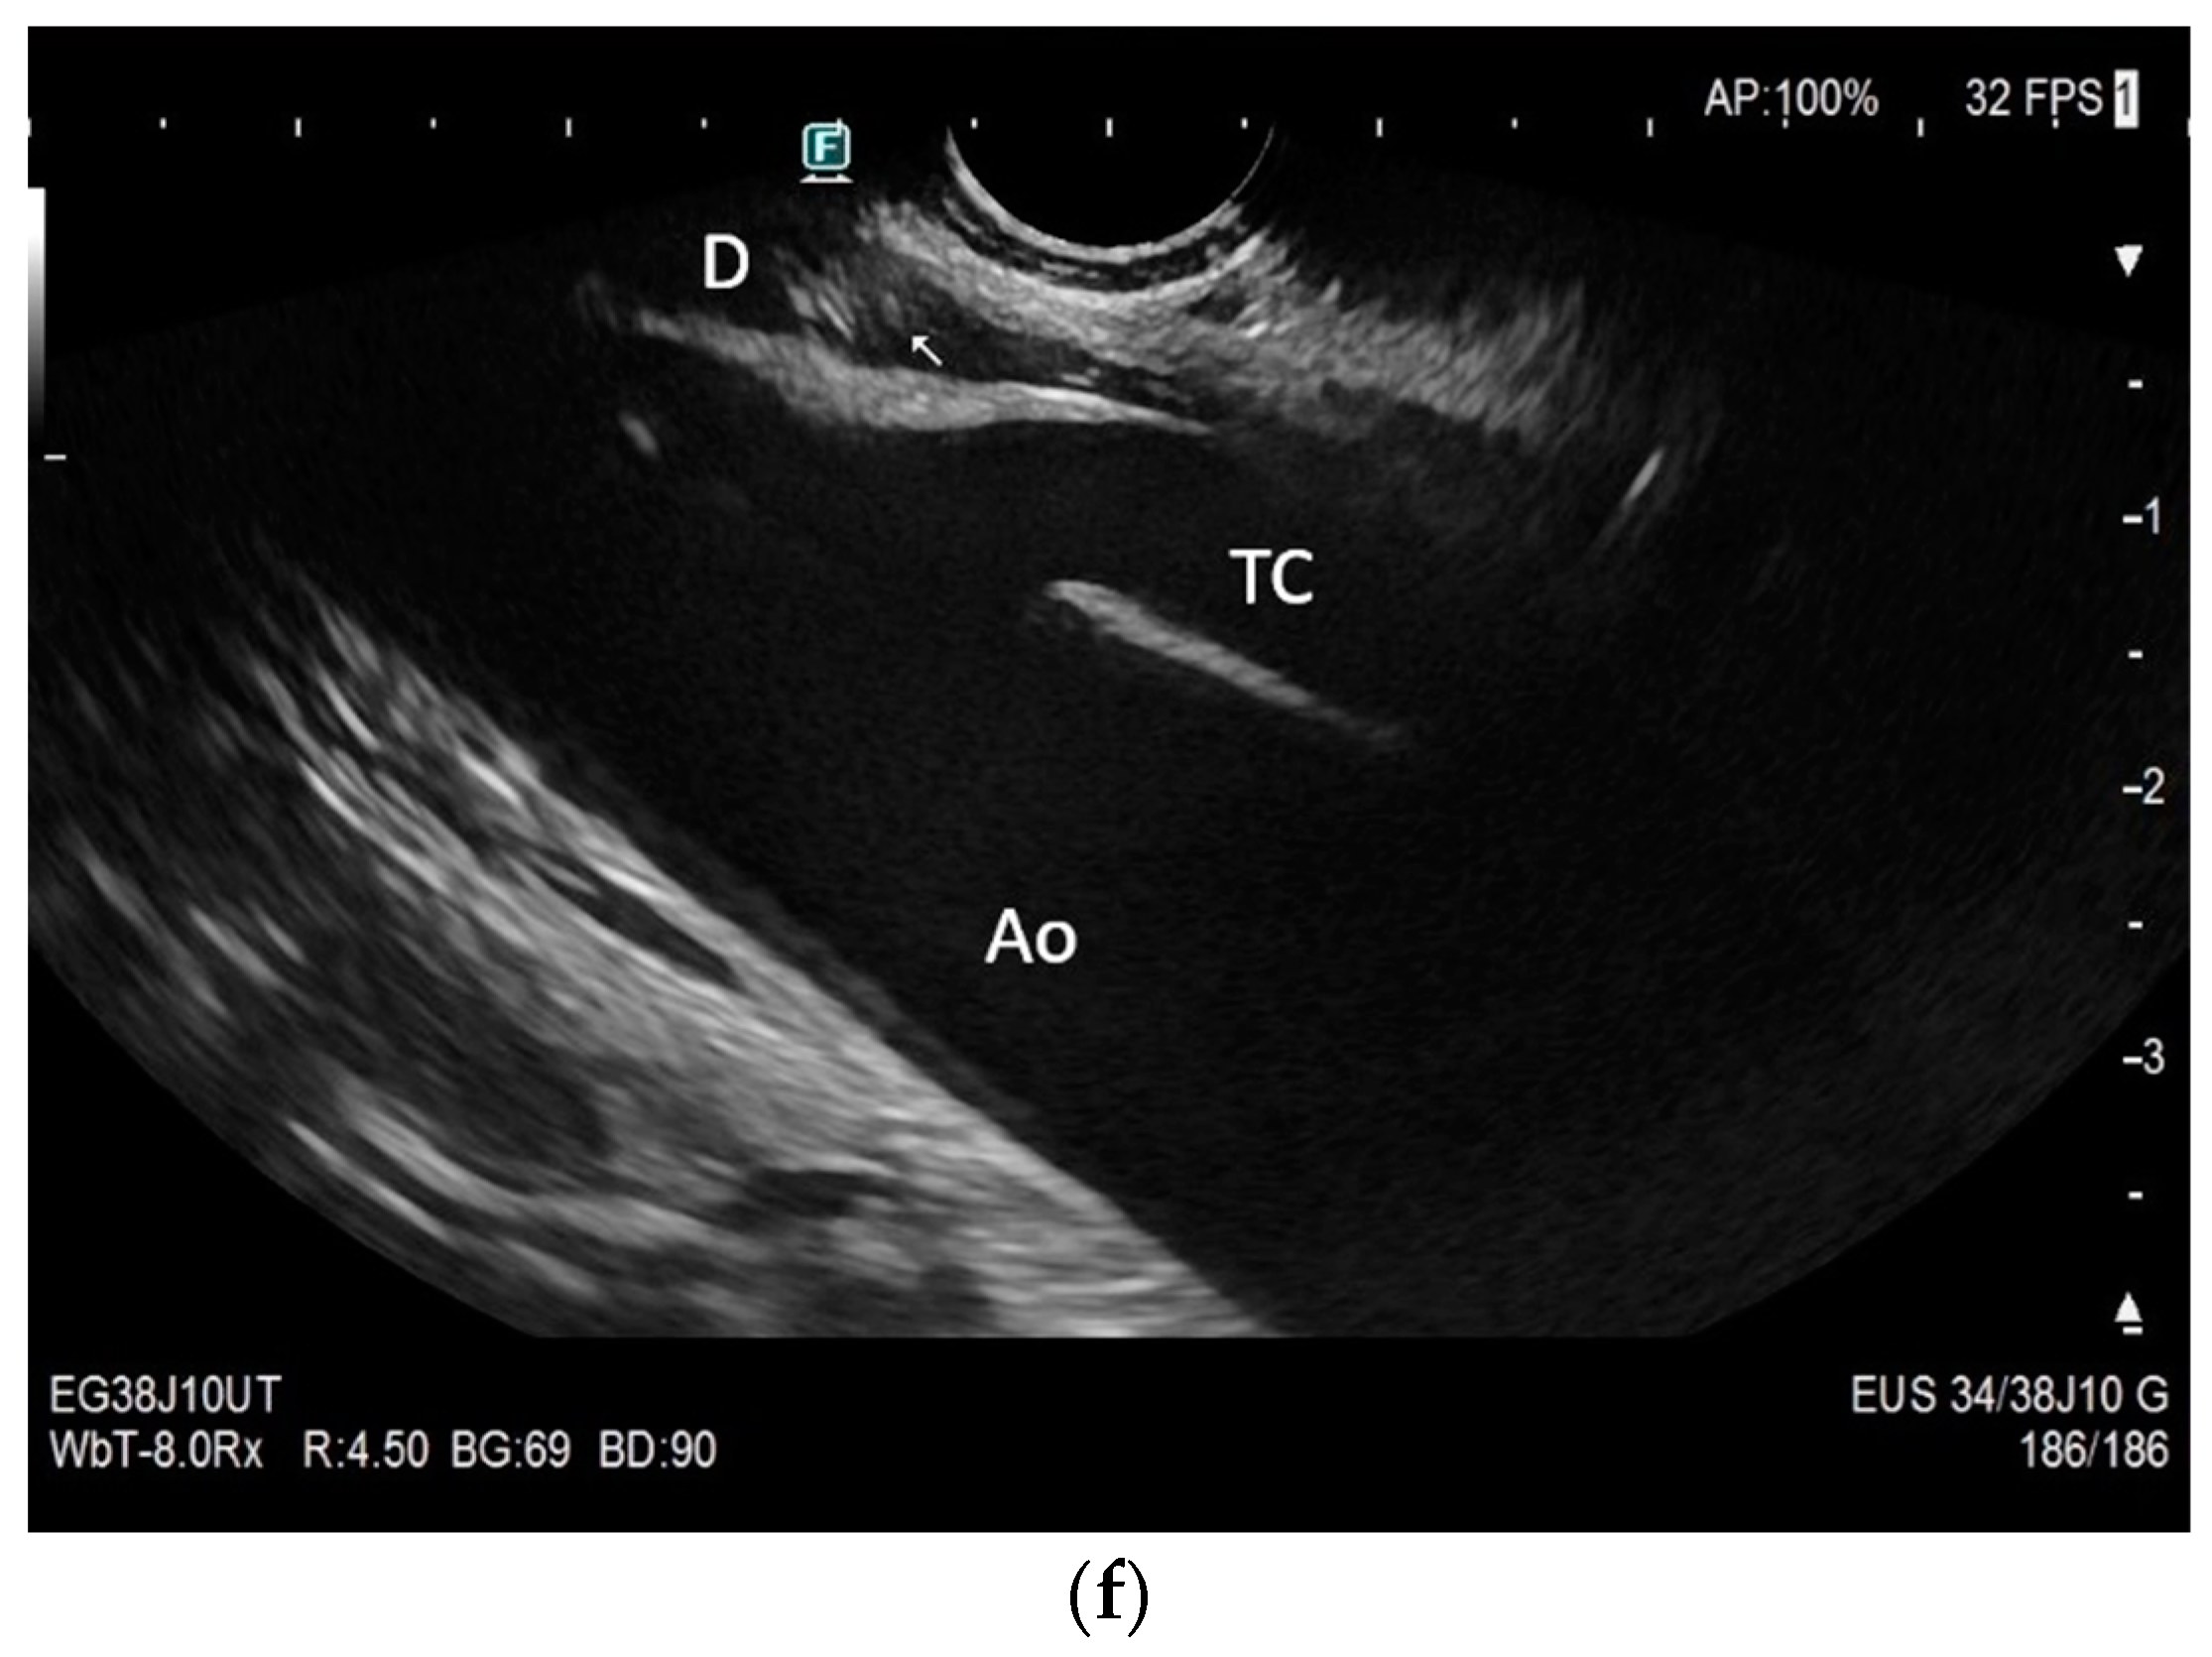

Subxiphoid: The diaphragm can be positioned directly subxiphoidally with a slightly sagittal transducer position on both sides next to the attachment to the sternum. The diaphragm limb can be demarcated to the right in the epigastrium in cross section between the aorta and the inferior vena cava. However, this is primarily of differential diagnostic importance, e.g., in relation to lymphomas, not for the actual assessment of the diaphragm (Figure 6).

Subcostal transducer position: An abdominal sector or cardiac transducer (2–5 MHz) is used in the subcostal window. This position is used to assess diaphragmatic excursion. The transducer is placed between the linea medioclavicularis and linea axillaris anterior. The diaphragmatic excursion can then be visualized and measured in M-mode (Figure 5). The gallbladder and inferior vena cava are important landmarks. It is important to guide the ultrasound probe as perpendicularly as possible. The M-mode axis should meet the diaphragm at an angle of 90%. In this position, diaphragm thickness in inspiration and expiration can also be measured using M-mode, and diaphragm shortening can be calculated. However, in normal adults, the diaphragm can usually only be visualized in this position using abdominal sector transducers and is less accurately delineated than with a linear transducer from the lateral side in the anterior axillary line.

The diaphragm can be assessed in two main transducer positions: lateral in the zone of apposition and subcostal. The zone of apposition is the section where the diaphragm is attached to the inside of the ribs. Measurements are taken in these both positions. In addition, the diaphragm can also be visualized subxiphoidally in the epigastrium in cross section. Depending on the depth of penetration, the examination is performed with an abdominal sector or cardiac transducer (2–5 MHz) or with high-resolution linear transducers. The choice of transducer depends on the depth of the penetration. Some authors choose transducers up to 15 MHz. We prefer a linear transducer up to 9 MHz. The assessment is conducted in B-mode ultrasound (US) and in M-mode US.